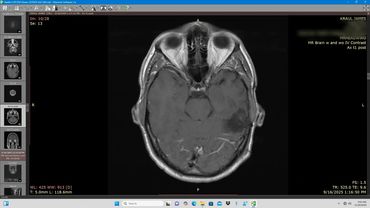

Axial MRI scan showing detailed brain structures including eye sockets and brain tissue.